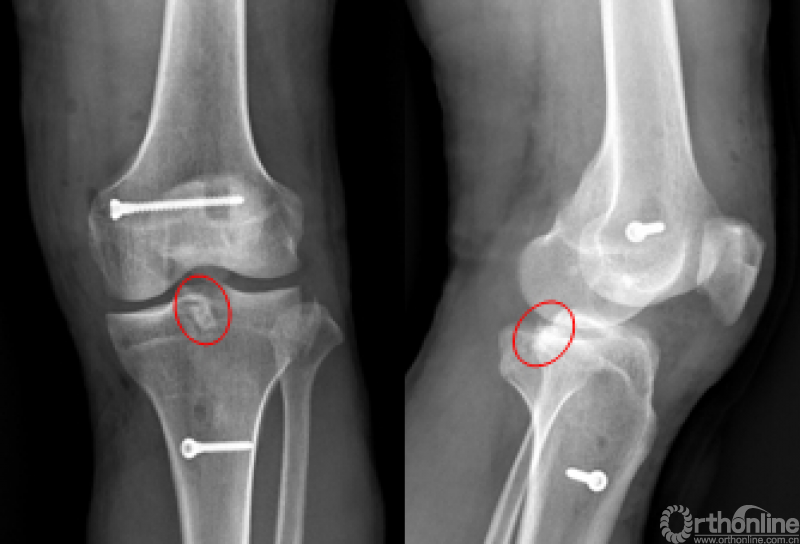

●8例均立即行X线检查

●6例全镜下操作标本行CT及MRI检查

●检验开槽位置、骨块稳定性及移植韧带走行是否合适

X线片

CT